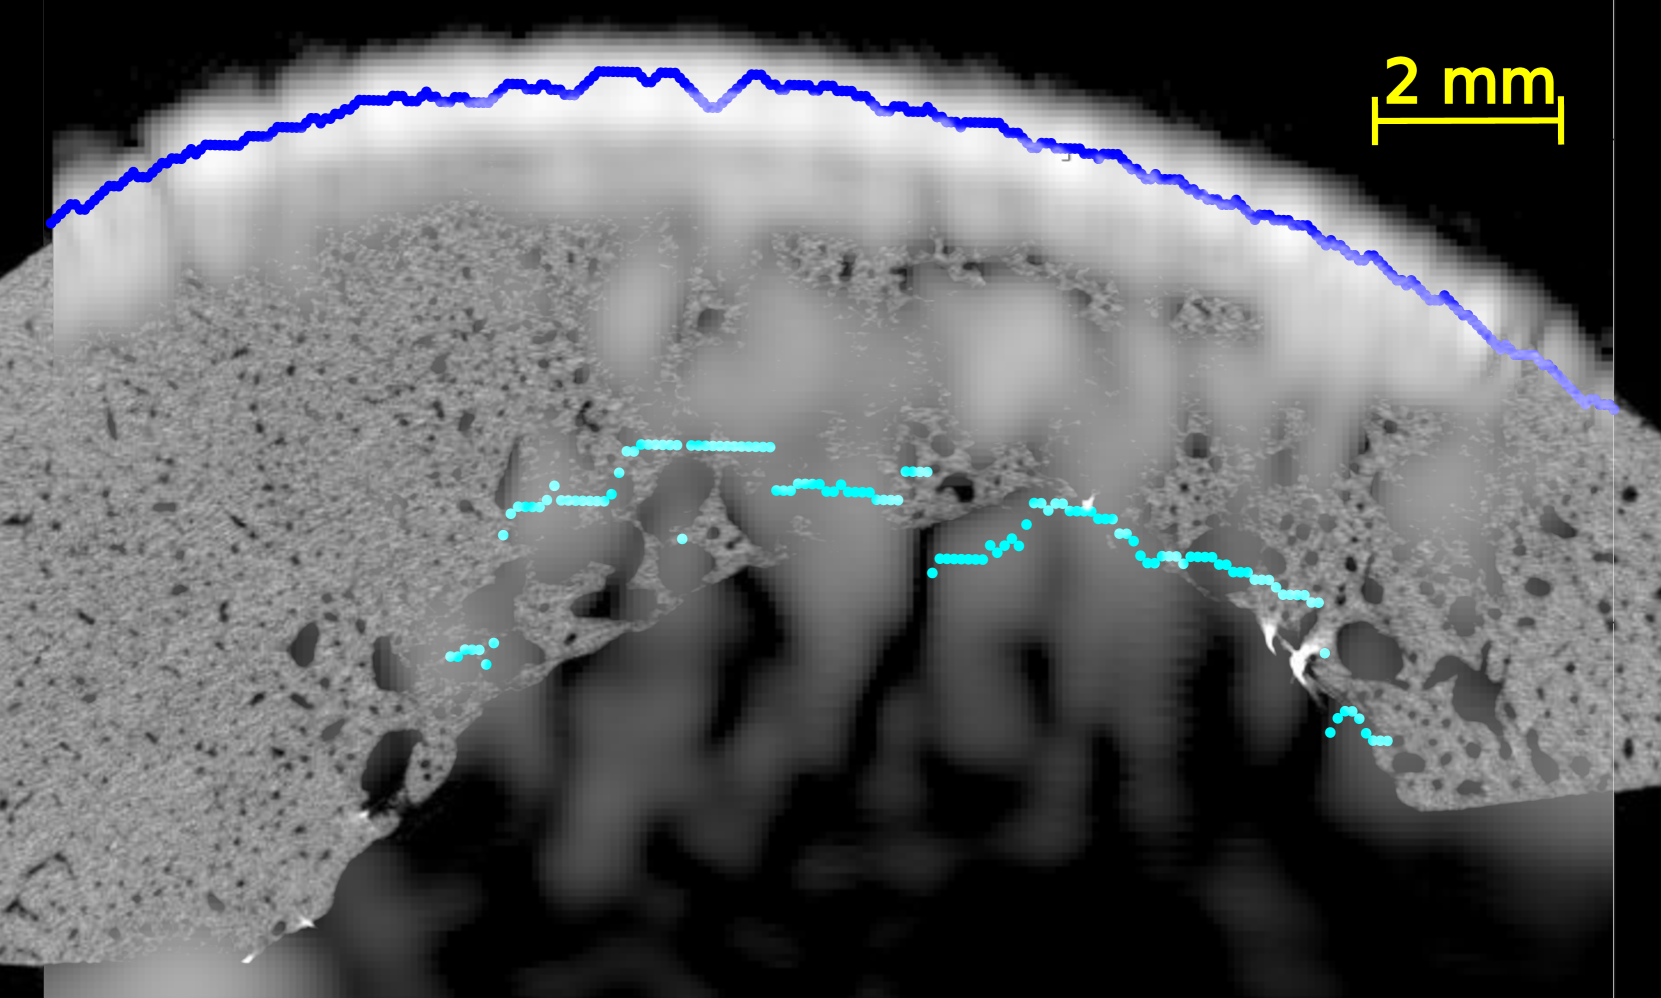

In all US images (Figure 4 and Figures S2-5 of supplementary materials), the periosteal surface appeared as a very bright line. The brightness of the endosteal surface was found to decrease with increasing porosity and with the presence of large pores. The endosteal surface was relatively bright in Samples 1 and 2 which had a small number of large pores and a small porosity; while the contrast of the endosteal surface was relatively weak in Samples 3 and 5 which had a higher porosity and some large pores near the endosteal surface (see the HR-µCT images (panels (a), (d), (g) and (j) of Figure 4). Segmentation with Dijkstra’s algorithm successfully delineated periosteal and endosteal surfaces for all measurement zones in all samples (see Figure 4). US images were aligned on HR-µCT images based on the periosteal surface segmentation. Periosteal surfaces from the US images accurately matched the periosteal surfaces segmented from the HR-µCT images: for all VOIs and all measurement repetitions, the root mean square error (RMSE) between the two segmentations was smaller than 0.3 mm, which value corresponds to half a US wavelength in water at 2.5 MHz (i.e., approximately the resolution limit).

We observed a good match between the segmented endosteal surface in the US image and the boundary of the cortex as seen in the HR-µCT image. The segmented endosteal surface closely followed the shape of the bone in the samples 1 and 2 which were the less porous and less heterogeneous. It is noteworthy that, despite the large thickness and complex geometry of sample 2, the endosteal surface was very bright in the US image. In the more porous and heterogeneous samples 3 and 5, the segmented endosteal surface followed the gross shape of the bone but was inside the cortex as seen in the HR-µCT image, above some large pores found close to the endosteal cortex boundary.

We evaluated the quality of US anatomical reconstructions and wave speed measurements across sixteen VOIs from bones of four individuals. Indeed, the bone of a fifth individual (sample 4) was too porous and heterogeneous to be effectively imaged through US. Our results indicate that the cortex boundaries and cortical thickness can be accurately determined for homogeneous and moderately porous VOIs, even for a thick cortex, as observed in samples 1 and 2 (mean thickness 2.9 and 5.9 mm and porosity between 5.0 and 12.3%, respectively). In these cases, the overlaying of US and HR-CT images showed that the segmentation of the surfaces in US images with the Dijkstra’s method closely aligns with the actual boundary, achieving thickness measurements with mean relative errors of 9 % and 4 %, respectively. In regions with higher porosity and larger pore diameters (samples 3 and 5 with porosity between 10.9 and 16.6% and Lg.Po.Dm between 224 and 307 m, respectively), the brightness of the endosteal surface is significantly reduced (from 7 dB to -5 dB). Nevertheless, Dijkstra’s algorithm was able to delineate endosteal boundaries that generally lied within the cortex, above the region with very large pores nearest to the endosteal surface. Consequently, in these cases, US-based cortical thickness measurements underestimated the reference (mean relative errors of 32 % and 47 %). However, for these highly remodeled bones with large resorption cavities leading to a trabecularization of the endosteal region, the delineation of the endosteal boundary as the end of the cortex and the beginning of the medullary canal is ambiguous, making it challenging to obtain a meaningful estimate of cortical thickness in the HR-CT images [5]. Another limiting factor in comparing cortical thicknesses determined from HR-CT and from US images lies in the slight differences in the regions of interest used for each VOI. The region of interest used for HR-CT images (Figure 2) were slightly larger than that used for US images. In the latter, as shown in Figure 4, the surfaces could only be reconstructed for a limited portion of the cortex due to the finite US probe aperture.

It is noteworthy that the inner cortex surface reconstructed with US was consistently within the bone, indicating that it effectively detects the most compact region corresponding to the tissue above the large pores in the endosteal region.

In highly porous samples exhibiting large pores, the reconstructed endosteal surface may show a reduced brightness and a lack of continuity. Indeed, previous simulations demonstrated that increased pore size has a strong detrimental effect on endosteal interface brightness [29], primarily due to the enhanced scattering by large pores. This ex vivo study corroborates these simulations results by providing an experimental proof that pore size is a major factor influencing intracortical US image quality.